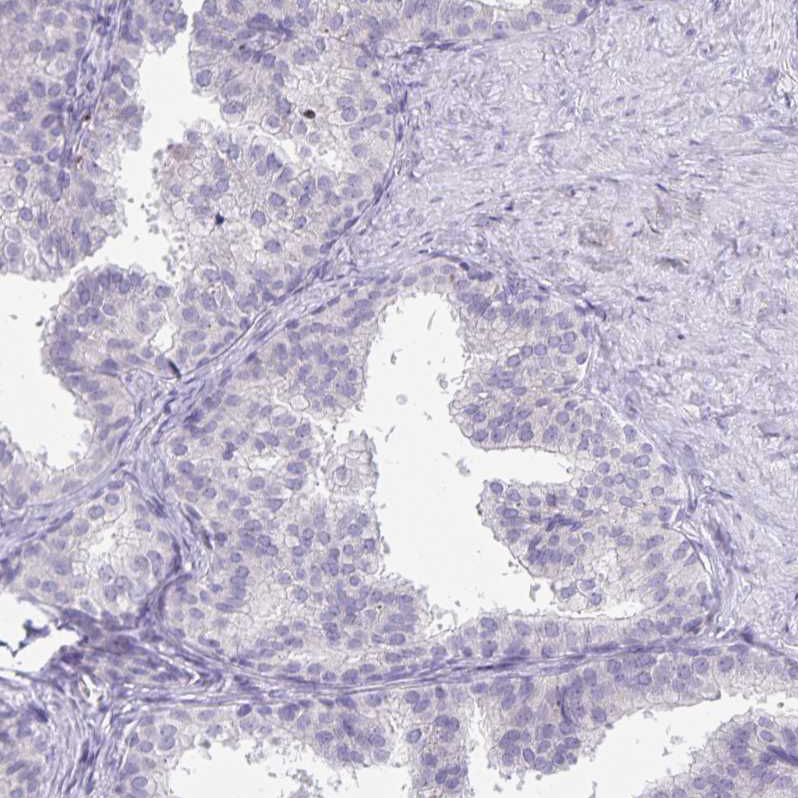

Immunohistochemistry analysis in human fallopian tube and prostate tissues using HPA052641 antibody. Corresponding DNAH9 RNA-seq data are presented for the same tissues.